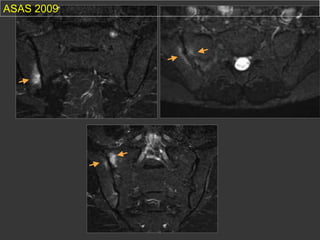

inflammatory lesions / ASAS criterias

sub chondral Œdema on 2 concecutive slices or 2

localisations on the same slice (STIR)

(Rudwaleit M et al. Ann. Rheum.Dis.2008)

ASAS 2009

enthesitis

Not in account

chronic Lesions

T1

sacro-tuberal Ligament